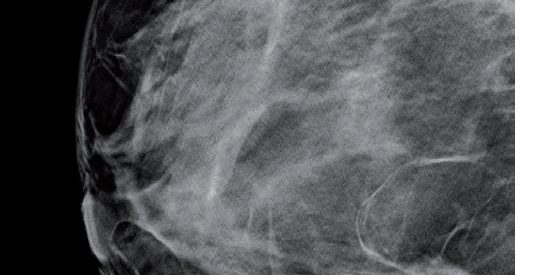

– Patiente de 57 ans asymptomatique, opacité dense du QIE du sein droit.

– La tomosynthese révèle une opacité dense bilobée à contours spiculés.

– Histologie : CCI.